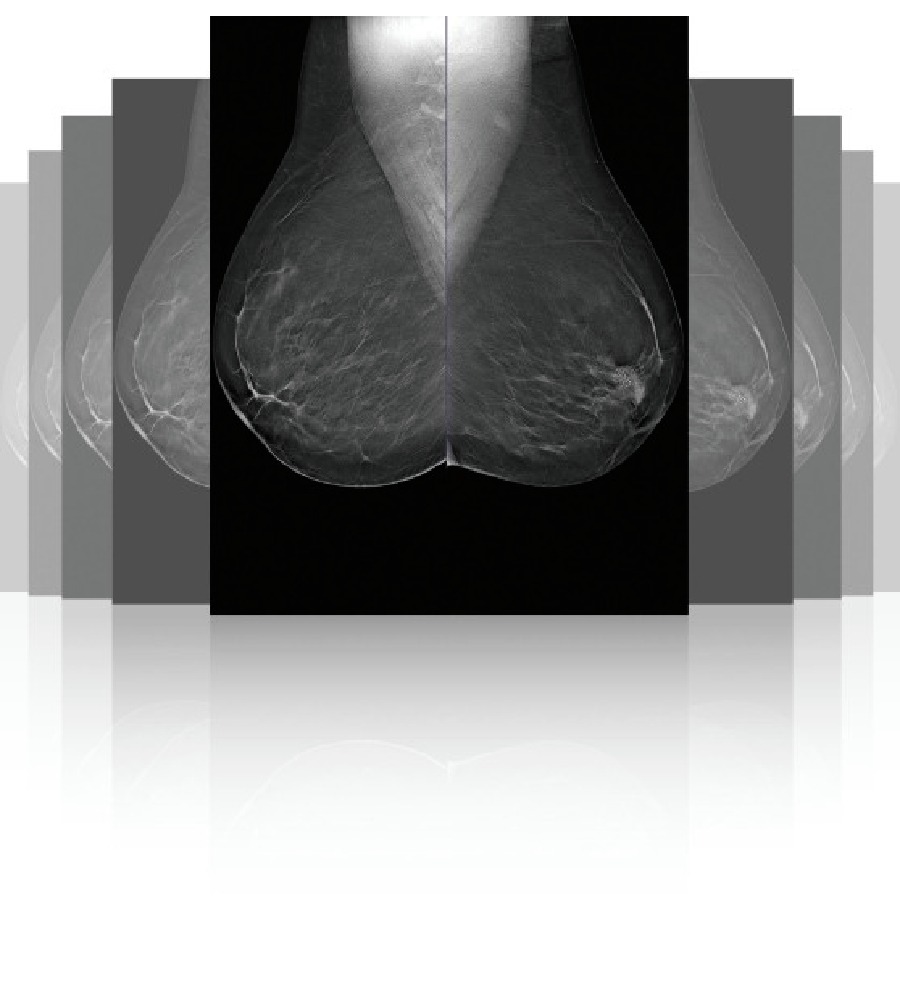

Ψηφιακός Μαστογράφος με Τομοσύνθεση Μαστού (DBT) Clarity™ 3D, Planmed

Το Planmed Clarity™ 3D φέρνει την επόμενη γενιά ψηφιακής μαστογραφίας, συνδυάζοντας κορυφαία ποιότητα εικόνας με υψηλή ακρίβεια στη διάγνωση. Ιδανικό για 2D screening, διαγνωστικές εξετάσεις 3D και στερεοτακτική βιοψία, προσφέρει ευέλικτες λύσεις για κάθε κλινική ανάγκη. Η τομοσύνθεση μαστού (DBT) επιτρέπει την ακριβή απεικόνιση πυκνών ή σύνθετων ιστών, μειώνοντας ψευδώς θετικά αποτελέσματα και βελτιώνοντας την πρώιμη ανίχνευση καρκίνου.